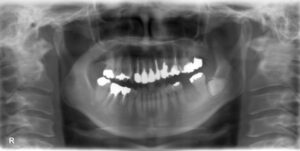

下顎大臼歯1本欠損症例

BEFORE AFTER 64歳女性/下1本欠損/インプラント埋込手術 【治療内容】 左下第一大臼歯の被せものが外れて来…